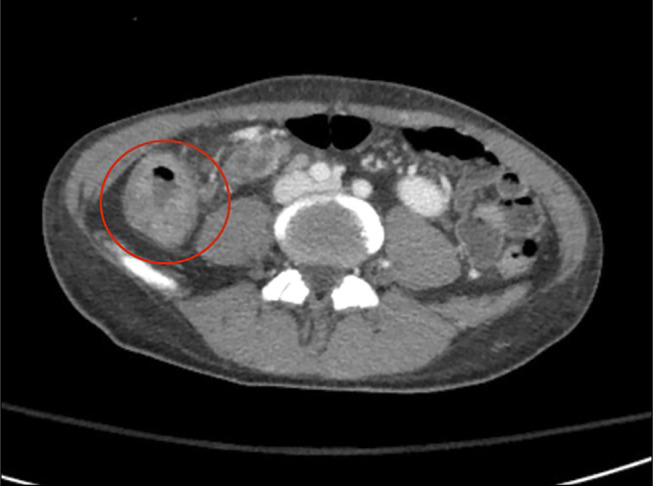

Gastrointestinal tuberculosis (GI TB) is an uncommon sequela of extrapulmonary TB, occurring in 1%-3% of TB cases worldwide. In the United States, many cases are seen in migrant populations or in immunocompromised individuals. The classic presentation of GI TB is nonspecific abdominal pain, and is not typically associated with significant, life-threatening bleeding. We present a case of GI TB complicated by severe lower GI bleed requiring vasopressor support in a newly emigrated patient with previously undiagnosed HIV/AIDS.